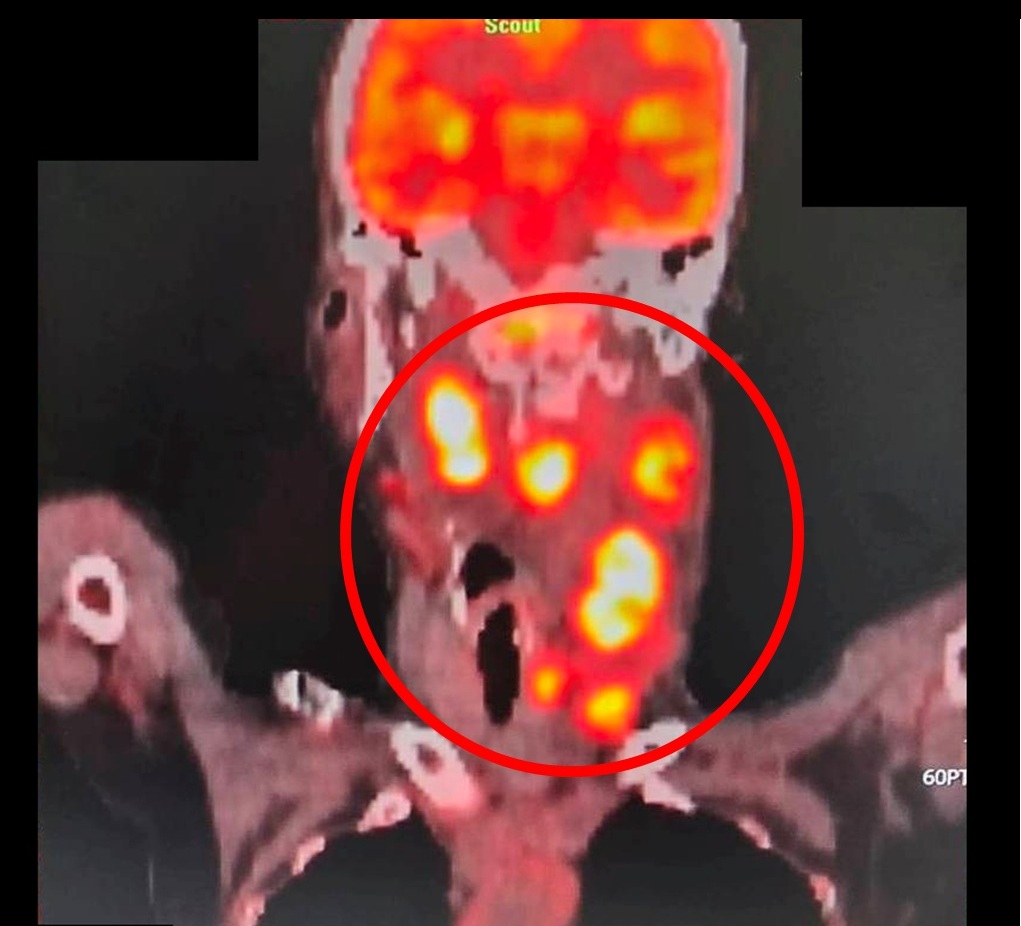

經正子造影檢查,病人為鼻咽癌第三期,且已轉移至頸部淋巴(紅圈處)/(照片:大千綜合醫院供)

很多人以為耳鳴只是過勞或耳朵發炎,但這可能是身體發出的癌症警報!50歲的林先生因左耳持續耳鳴且聽力下降,原以為只是單純聽力變差,前往耳鼻喉科檢查。沒想到,經鼻咽內視鏡檢查,竟發現鼻咽部有腫瘤,轉介至大千綜合醫院進一步核磁共振檢查後,確診為鼻咽癌第三期,且癌細胞已轉移至頸部淋巴。所幸,經大千癌症醫療團隊治療後,追蹤至今三年多病情控制良好,無復發或轉移的情形。